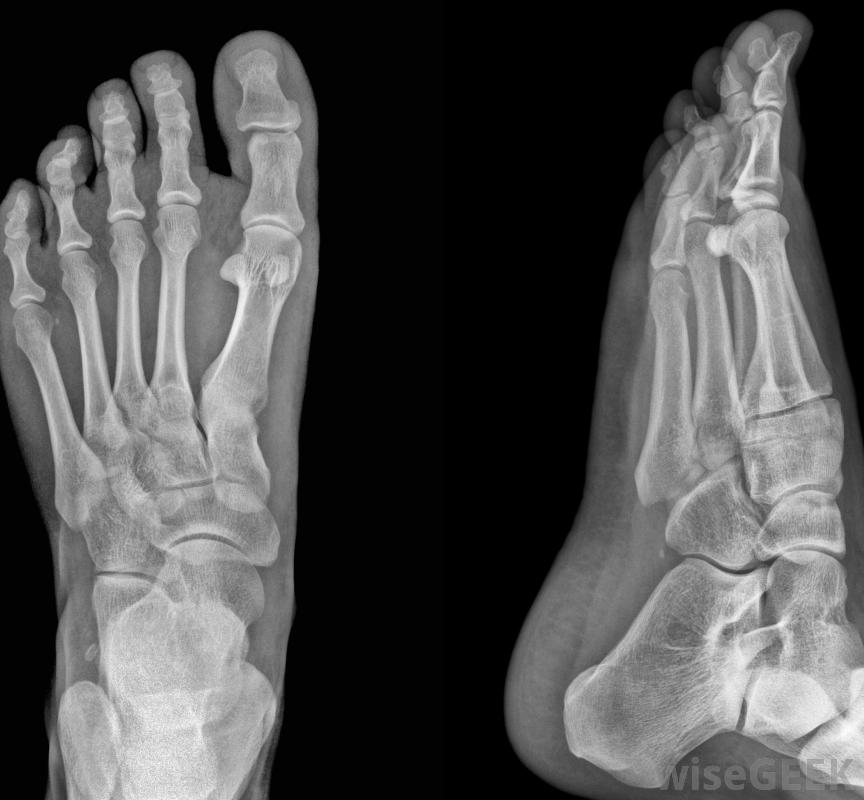

骨刺,也被称为骨赘,可以发生在骨骼系统的任何地方,但在脚中很常见。脚趾或脚后跟上的骨刺可能是由于周围韧带或软骨的损伤或外伤,或者是由于老化和使用的自然结果。它们可能是由于骨的过度生长引起的,通常是在两块骨头相遇的关节处脚趾骨刺的症状可能是患处疼痛、肿胀或触痛骨刺可发生在任何脚趾上,但最常见于第五脚趾。在许多情况下,脚趾上的骨刺可能没有任何症状。在某些情况下,患处确实会疼痛。骨赘引起的疼痛不是由"骨刺"本身引起的,但由于与另一块骨头、神经或软组织的摩擦而产生。在极少数情况下,骨刺可能会折断,卡在关节之间,从而导致关节不能活动。可以使用x光片来确认骨刺。治疗脚趾上的骨刺的方法包括抗炎药物治疗、物理治疗和用特殊的靴子或脚支撑暂时静止不动。如果这些措施结合起来不起作用结果是,如果疼痛是慢性或严重的,或者影像学检查显示周围神经、韧带或肌腱受损,则可能需要手术。脚趾骨骨刺的手术通常很简单,可能需要用手术缓冲液抚平骨刺,并移除全部或部分趾甲在某些情况下,骨刺是慢性脚痛的根本原因。在许多情况下,脚趾上的骨刺没有任何症状如果疼痛很小或没有疼痛,除了通过限制身体活动暂时让脚休息之外,可能没有什么需要做的。穿着舒适、合脚、不扭伤脚趾的鞋子也有助于减轻由骨刺引起的轻微不适患有骨刺的人在上下楼梯时可能会有困难。骨刺最常见于第五趾,尽管它们中的任何一个都可能发生脚趾上的骨刺可能需要手术,尽管手术通常很简单。